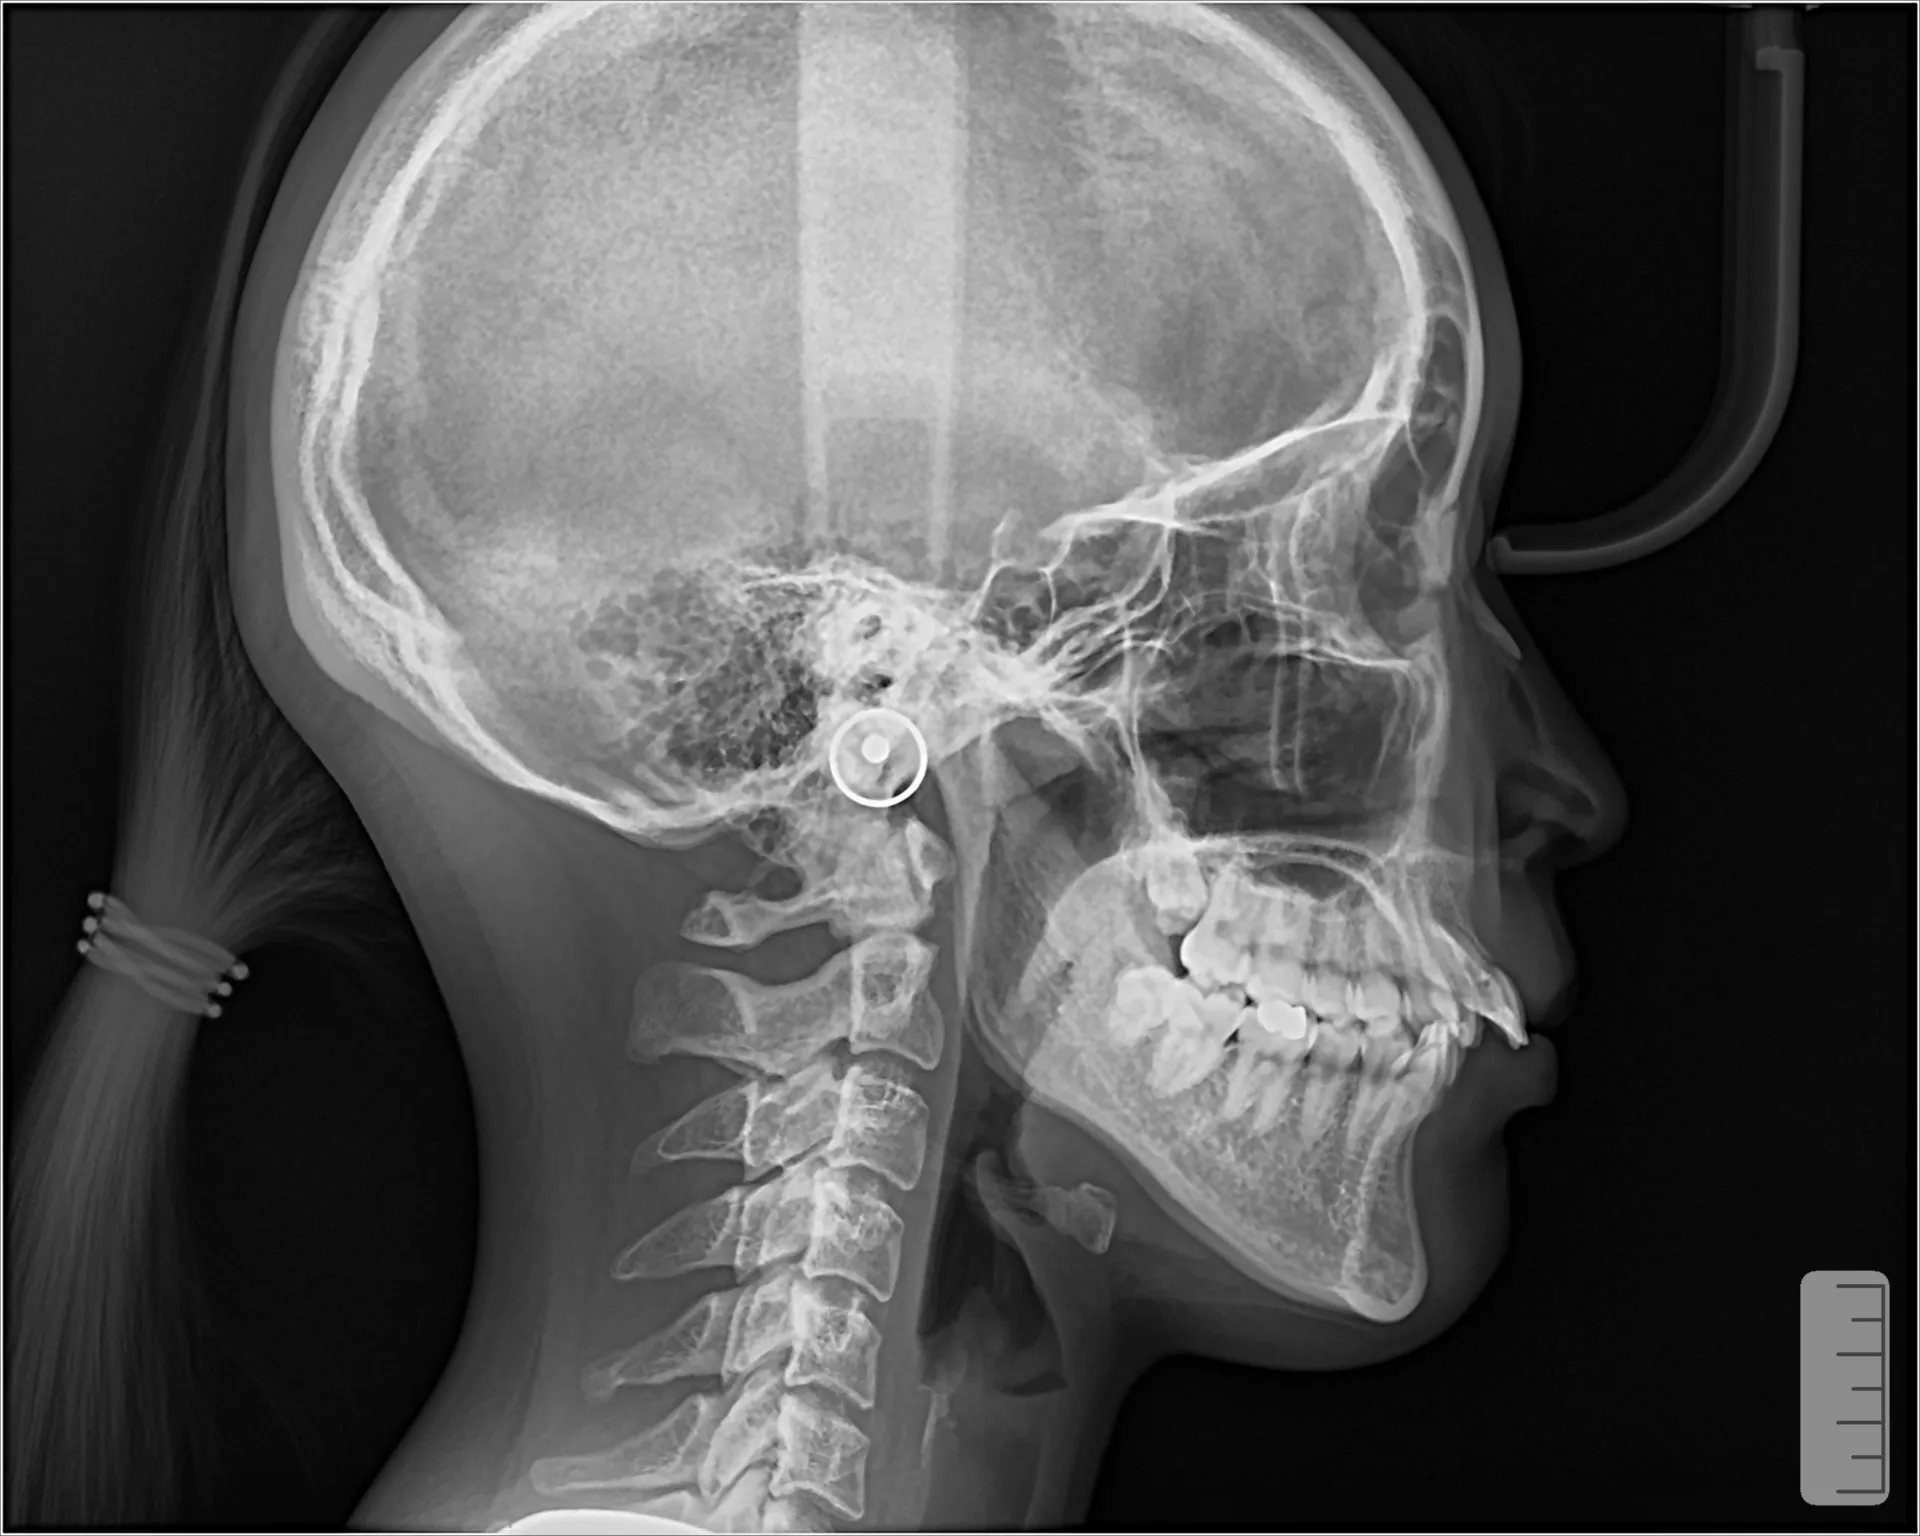

大きく飛び出してしまった前歯の矯正と変色の治療を希望された症例をご紹介いたします。

しかしながら、患者様が遠方に引越すことになり当院での治療はここで終了となってしまいました。

もう少しで矯正も歯の変色も変えられることができたのですが、移動費もままならないので残念ながら転医として他の歯医者さんで引き継いでいただく形となりました。